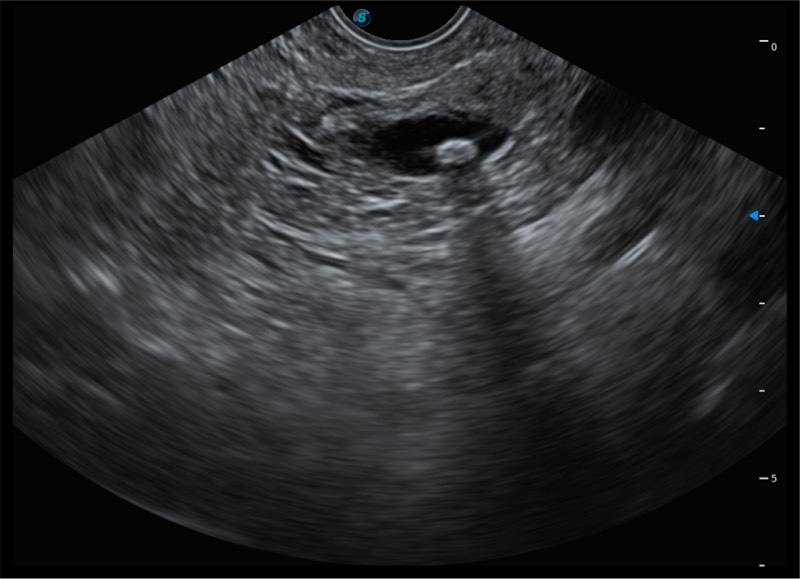

• 4.0mm大钳道

• 12.6mm先端部外径

• 150°超声扫描角度

• 4-12MHZ宽频输出